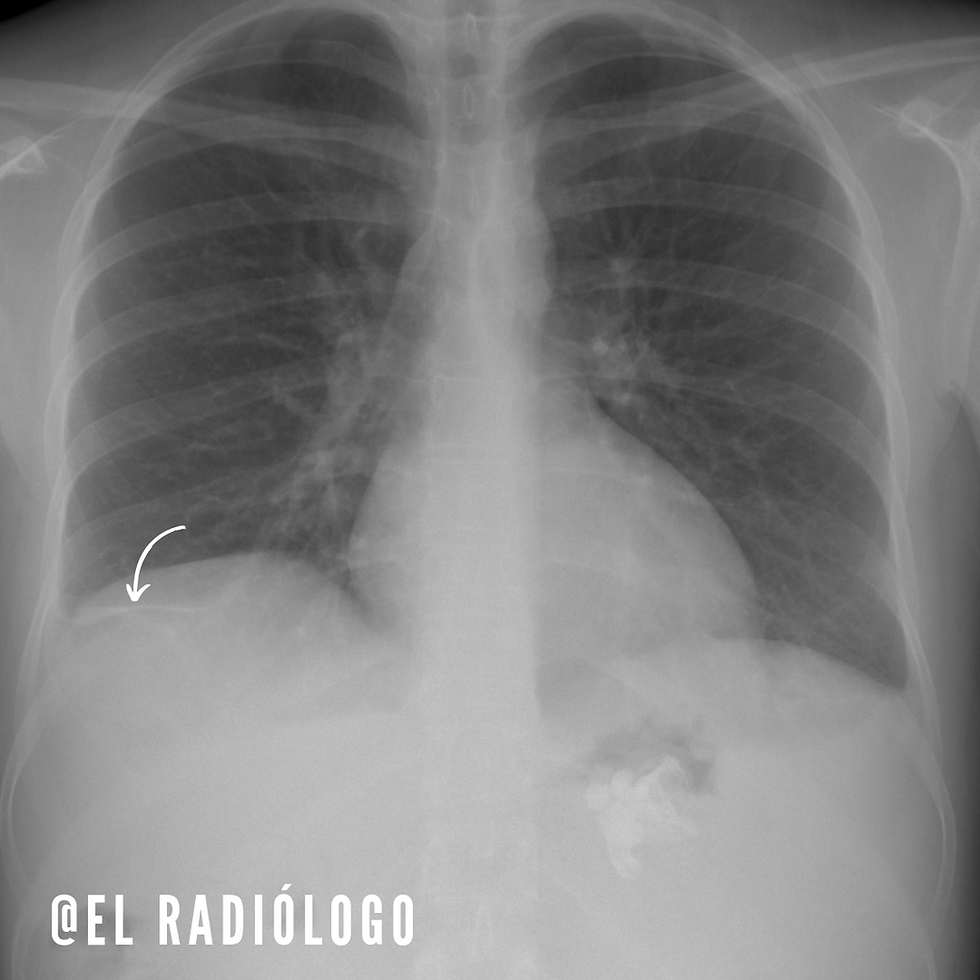

Atelectasias subsegmentarias

Las atelectasias subsegmentarias, también llamadas discoides o en forma de placa, se manifiestan típicamente como una opacidad lineal con densidad de tejidos blandos.

Tiene un grosor entre 1 a 3 mm y una longitud entre 4 a 10 cms.

Su ubicación más común son el lóbulo medio e inferior, este último más comúnmente.

Aunque en la mayoría de los casos se encuentra con una orientación vertical, no es raro encontrarlas oblicuas; lo anterior dependiendo de la zona del pulmón afectada.

Pueden ser simples o múltiples, en un solo lado o bilateral.

Este tipo de atelectasias se encuentran más comúnmente en pacientes con disminución de la excursión diafragmática, como aquellos con alguna enfermedad inflamatoria o estados post quirúrgicos abdominales.